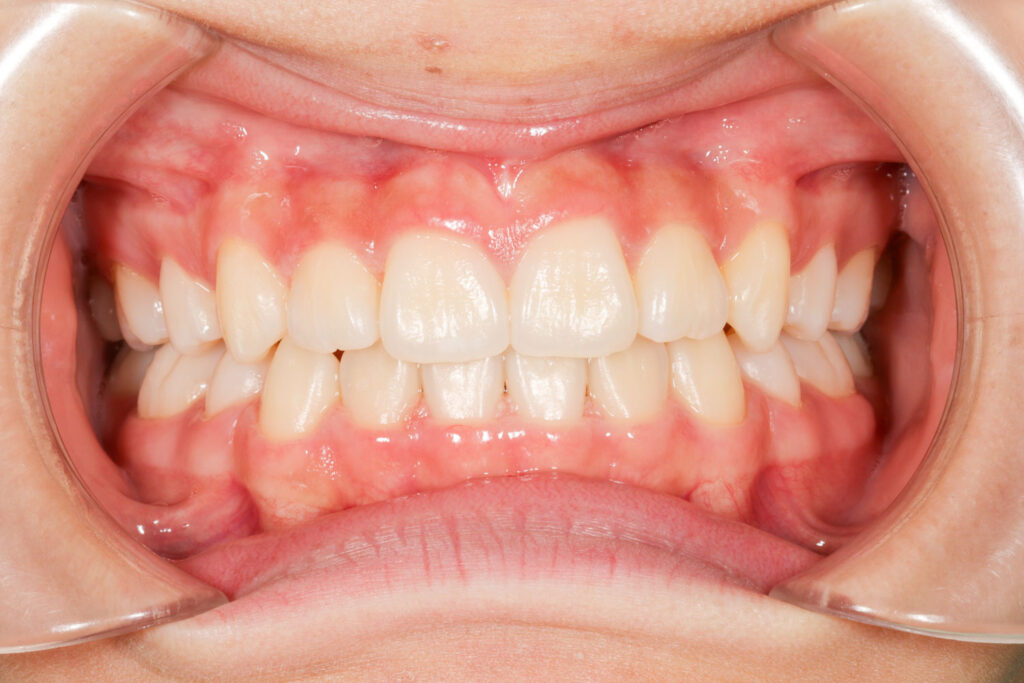

Before

年齢 10代

治療装置 上は裏側の矯正装置(ハーフリンガル)

治療内容 上下左右4本抜歯

治療期間 2年8か月

リスク 歯の移動に伴う痛み、歯肉退縮、歯根吸収、歯肉炎、虫歯

主訴 八重歯が気になる

症状 叢生(ガタガタ)

治療回数 33回程度

総額費用 125万円程度